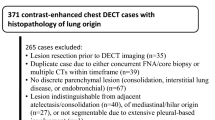

A retrospective database query was executed to identify oncologic patients (≥ 18 years) who underwent clinically indicated, contrast-enhanced, venous phase SDCT of the chest and who were diagnosed with visually uncalcified, metastatic or benign lung nodules according to the radiological report. Subsequently, lung nodules with a diameter equal or greater than 5 mm were selected by an experienced radiologist and all nodules were correlated with ground truth as indicated below; if ground truth was absent, patients were excluded. Figure 1 shows the workflow for inclusion and exclusion of study subjects.

183 cancer patients (96 men and 87 women, mean age 63.2 ± 13.0) who underwent SDCT of the chest were included: 85 patients with 161 benign lung nodules and 98 patients with 425 lung metastases. Median time of available imaging follow-up for ground truth correlation was 22.5 months, ranging from 6 months to 79 months. Table 1 gives an overview on patient characteristics. 425 metastases and 146 benign lesions were used for training and testing comprising approximately 70 and 30% of the data, respectively. Accordingly, the training group was composed of 105 benign lesions and 294 metastases, while the testing group comprised 41 benign lesions and 131 metastases. Figure 2 gives an overview on the methodological workflow of the study.